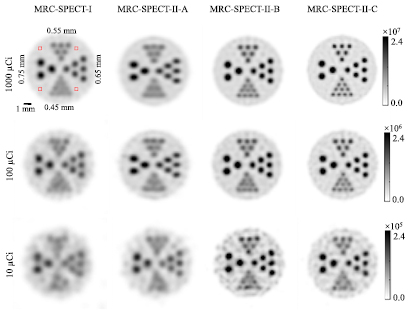

In order to evaluate the imaging performance of MRC-SPECT-II and different configurations, we have carried out a series of simulation studies and the results are shown in figure 5.

Figure 5. Images of a resolution phantom reconstructed at similar variance level; the filter FWHMs for the MRC-SPECT-II-C images at 1 mCi, 100 μCi, and 10 μCi were 0.3 mm, 0.4 mm, and 0.5 mm respectively. We varied the filter size of other systems to ensure their variance in the ROI (the four square regions, each having 4 × 4 × 10 (axial) voxels, marked in the upper left figure.) was similar to that of the corresponding MRC-SPECT-II-C images.

Standard image High-resolution imageIn figure 5, we found that the detector resolution played a significant role in improving the imaging qualities of MRC-SPECT-II. Given 1000 μCi activity, the features of the 0.65 mm hot rods were blurred by MRC-SPECT-II with the prototype HPWF (MRC-SPECT-II-A), while the features of the 0.45 mm hot rods were clearly resolved by MRC-SPECT-II with the proposed HPWF (MRC-SPECT-II-C). When the activity was reduced to 10 μCi, the reconstructed images of MRC-SPECT-II-A were distorted, but those of the proposed HPWF could still resolve features of 0.55 mm. Comparing the results of MRC-SPECT-II-B and MRC-SPECT-II-C, we found that DOI information allowed the system to resolve high resolution features. In the 1000 μCi case, DOI information (MRC-SPECT-II-C) could improve the system resolution from 0.55 mm to 0.45 mm.

Figure 5 compares images obtained with MRC-SPECT-I and MRC-SPECT-II. At high activity (1000 μCi), MRC-SPECT-II-C with proposed HPWF detector could achieve a resolution of around 0.45 mm, while MRC-SPECT-I only delivered 0.55 mm resolution images at the similar variance. When the phantom activity was reduced to 10 μCi, all of the hot rods in MRC-SPECT-I were distorted, while MRC-SPECT-II could still resolve features of 0.55 mm. Clearly, high system sensitivity and rich angular sampling made MRC-SPECT-II more immune to noise.